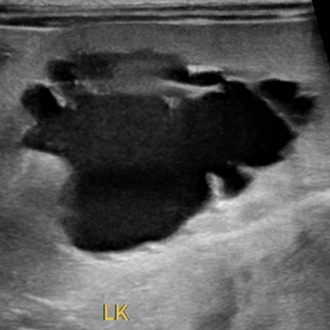

비뇨기계 수술

배뇨 곤란, 혈뇨, 결석 등 비뇨기 문제는 통증뿐 아니라 신장 기능에도 영향을 줄 수 있습니다.

원인을 확인한 뒤 아이 상태에 맞는 치료를 진행합니다.